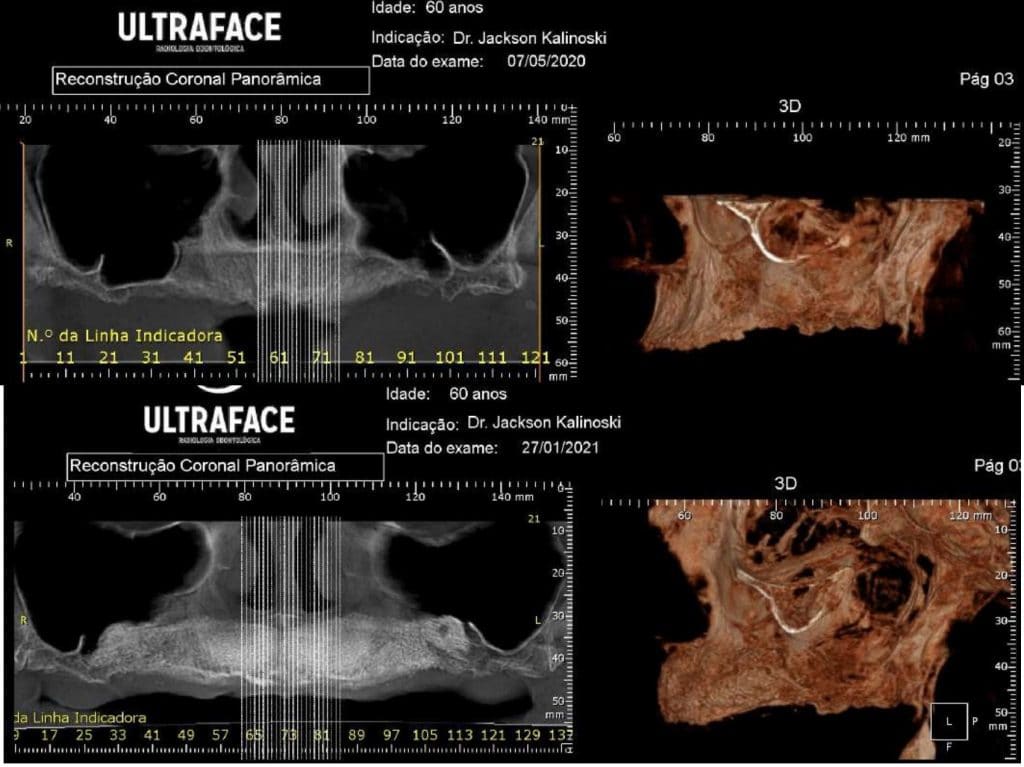

Olá colegas, aqui está um caso didático de reconstrução óssea total da maxila, levantamento do seio maxilar bilateral e bloqueio espesso com aplicação do conceito de PRF e Biotensigrity.

Após 6 meses de maturação óssea e implantes instalados com torque médio de 35 N / cm2.